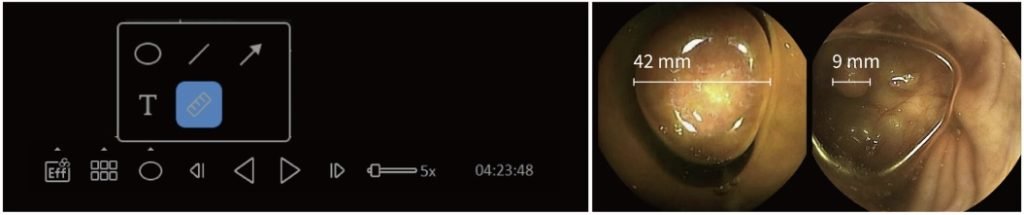

VUE Smart je opremljen mernim alatom. Izbočene lezije debelog creva su najčešće abnormalnosti kod bolesti debelog creva, kao što su polipi, tumori i variks. Merenje veličine ovih lezija je neophodno za lečenje pacijenata.